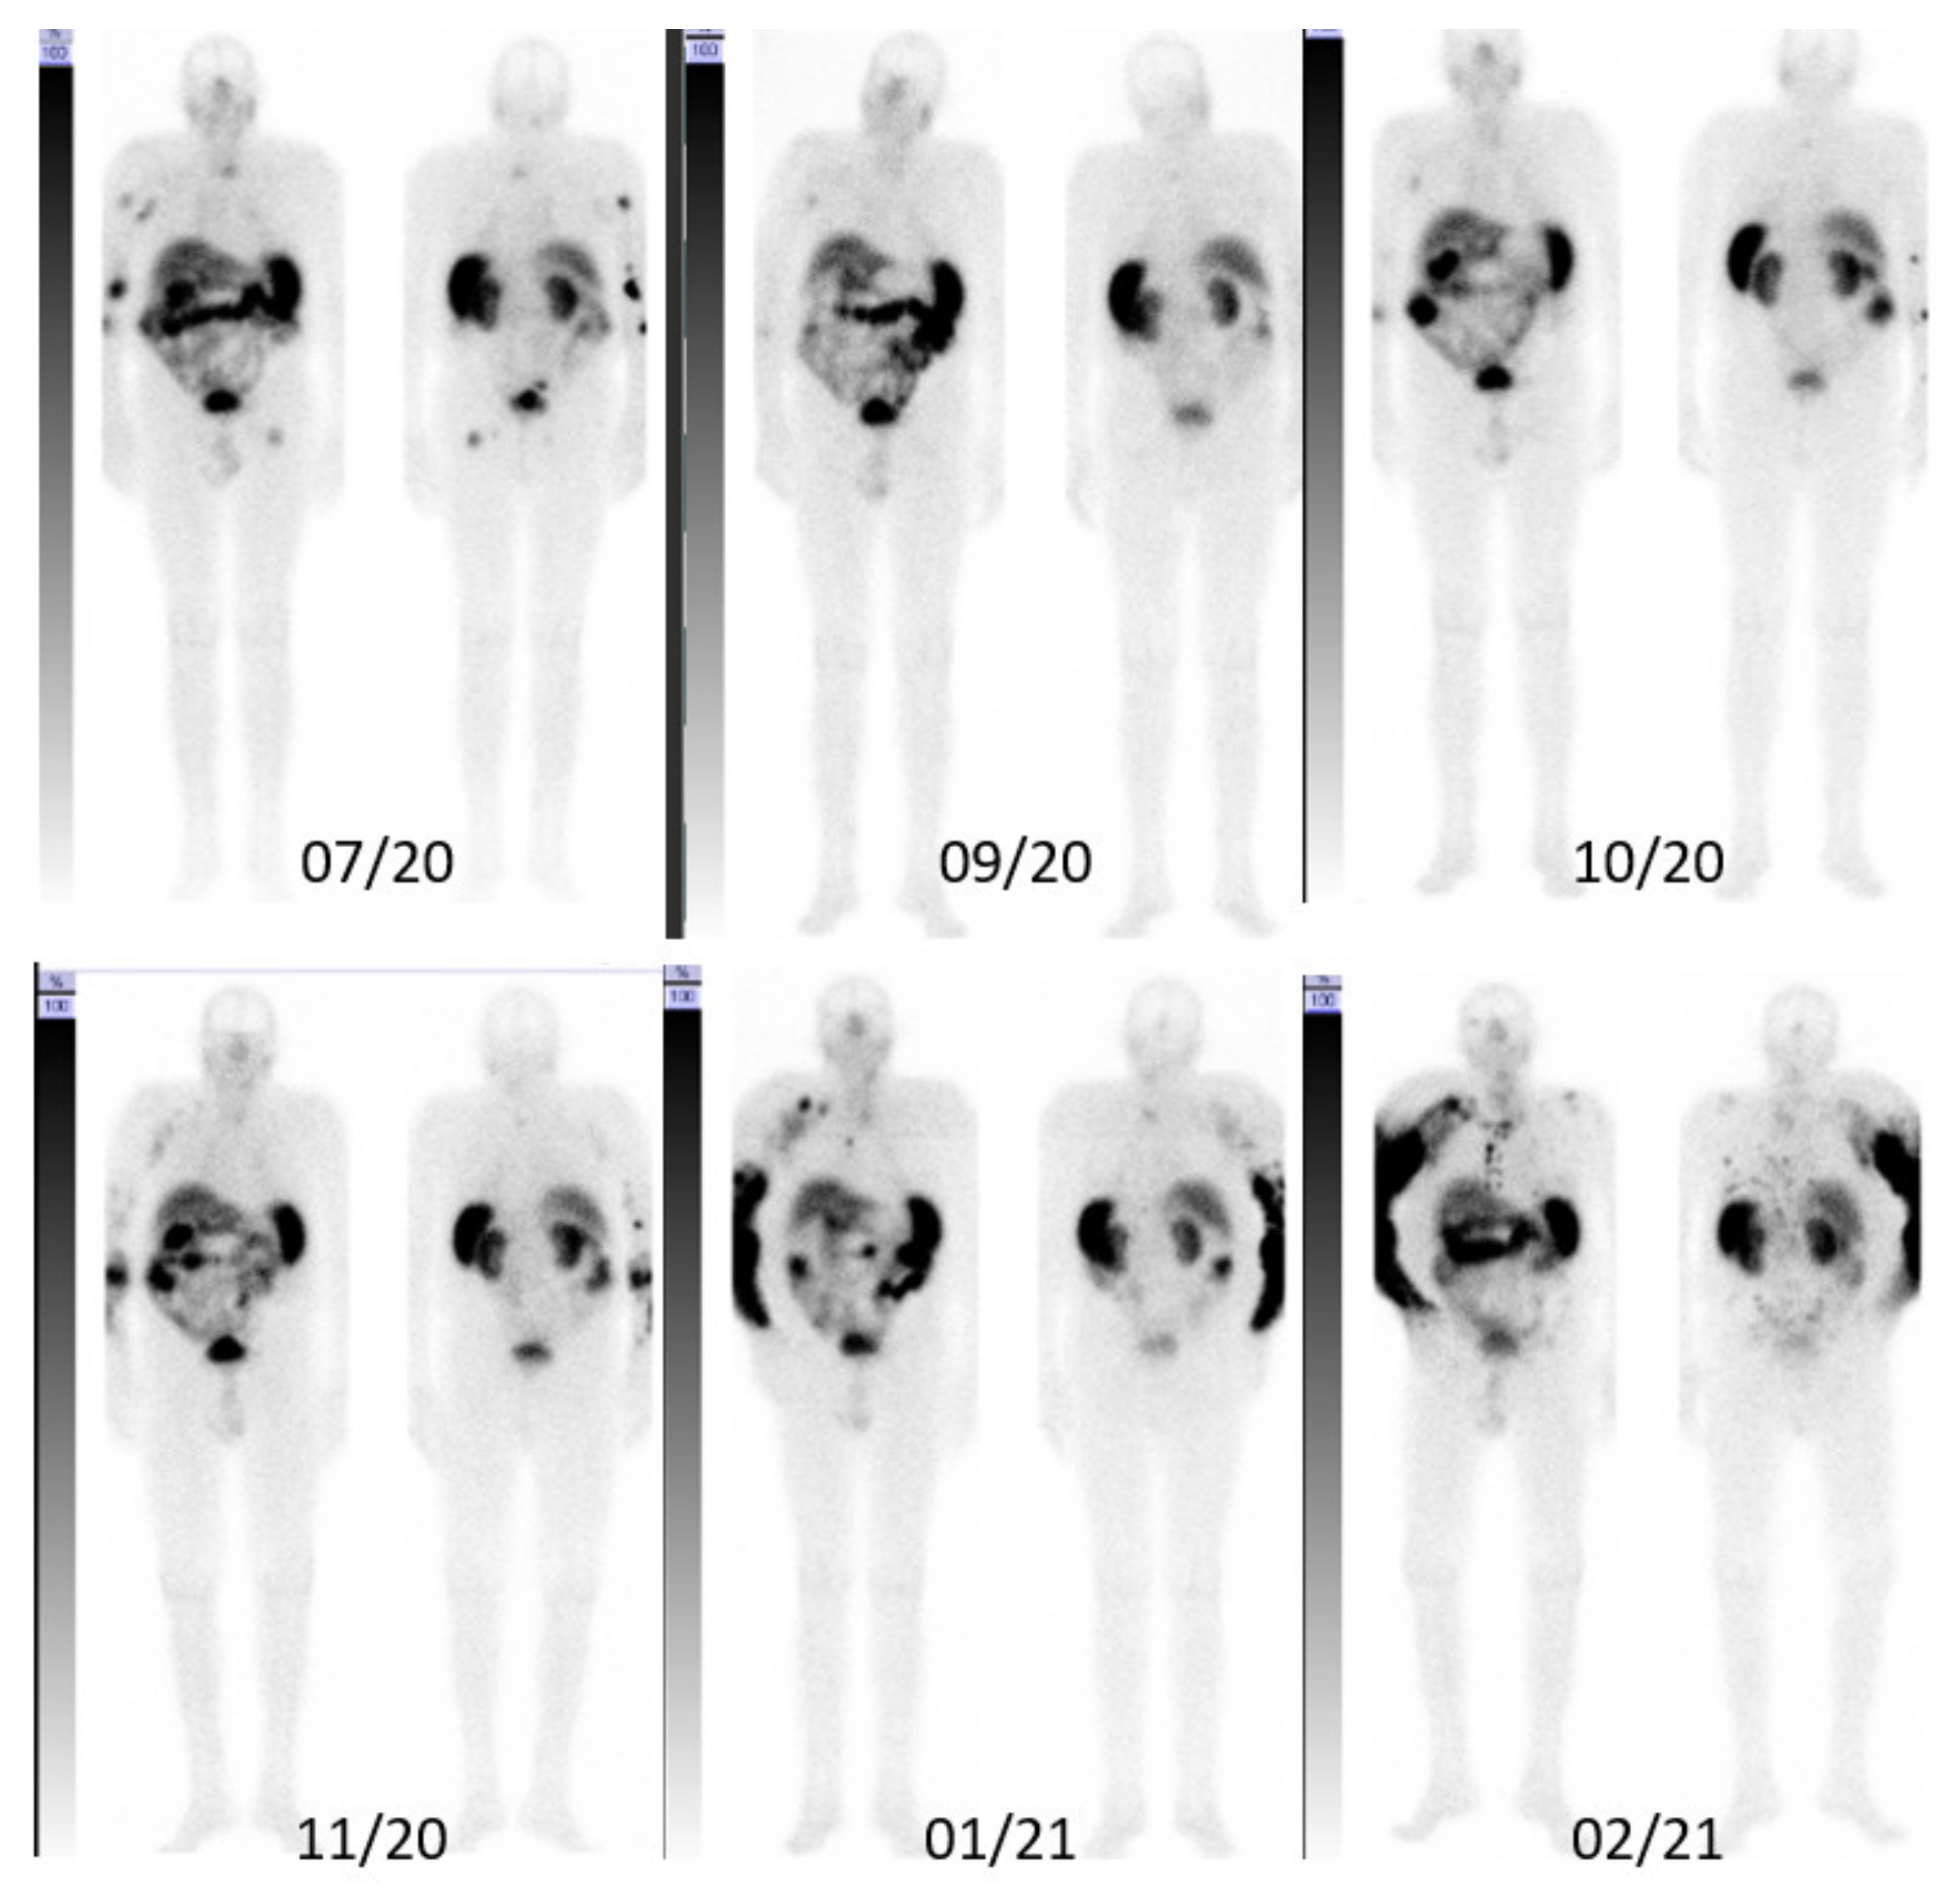

3. Case Description